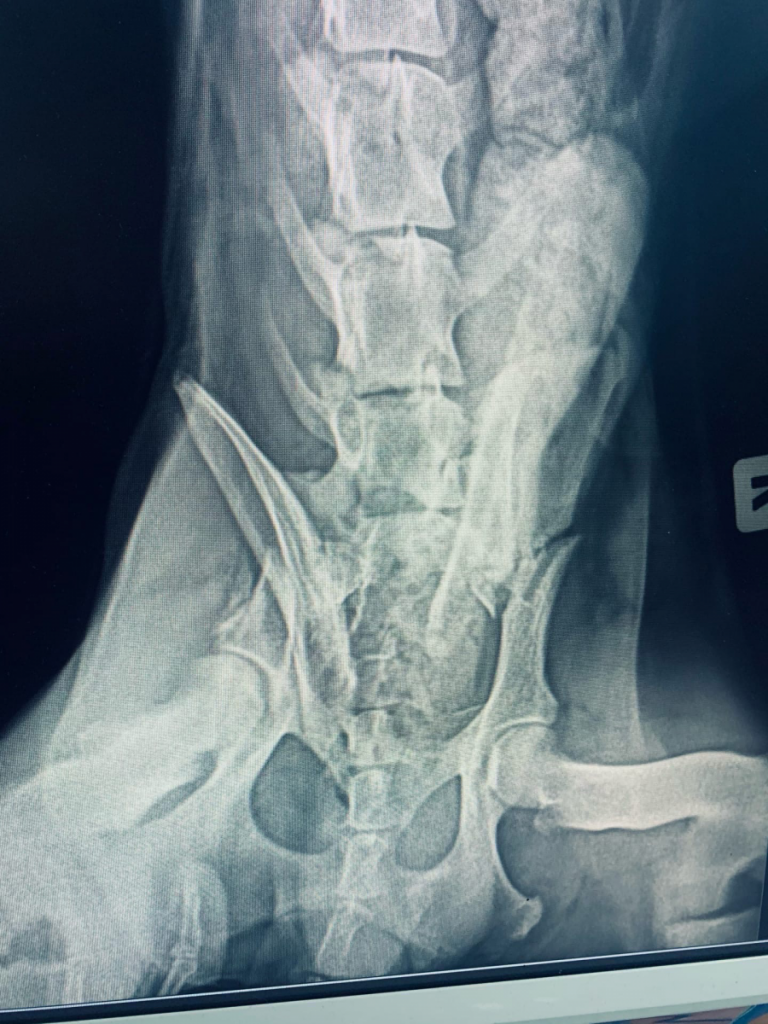

Волонтеры отвезли собаку в Москву, где ему провели очень сложную многочасовую операцию. Оказалось, у сбитого пса перелом таза. И это ДТП — не первое в его недолгой жизни, о чем говорят  рентгеновские снимки.